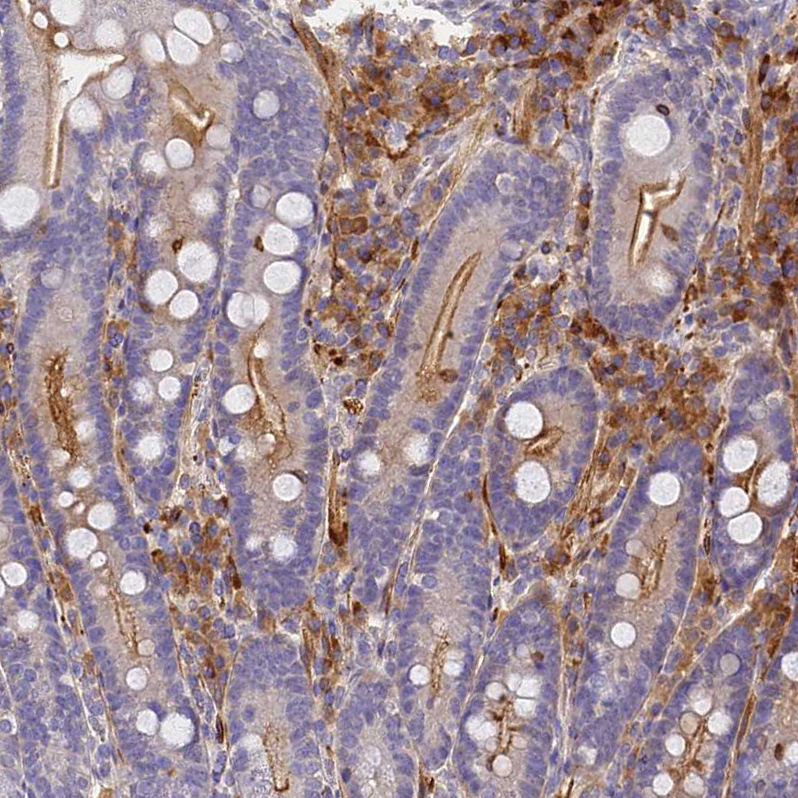

Immunohistochemical staining of human lymph node shows strong membranous and cytoplasmic positivity in germinal and non-germinal center cells.